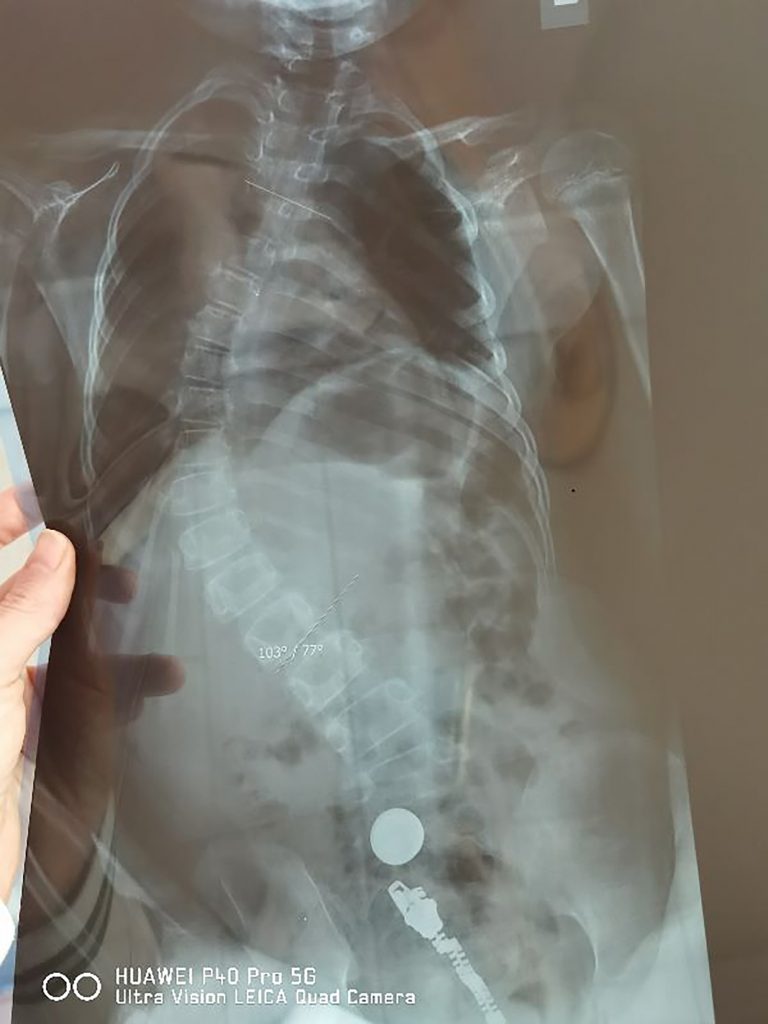

Sramota lekara sa "Banjice": Odbili da pomognu maloj Sonji (8) iz najgoreg mogućeg razloga, uz još gore obrazloženje autor: Ana Marković Društvo 19. okt. 2022. 21:16 0 Podeli vest: Naše osmogodišnje dete je 100 odsto invalid, a kada joj je pre tri godine dijagnostikovano 100 stepeni krive kičme, usled teške bolesti, lekari nam nisu dali pozitivno mišljenje za operaciju u inostranstvu, jer bi u tom slučaju Fond morao da iskešira ogroman novac, pa ona kao pacijent nije ostvarila nijedno svoje pravo, a lečenje od tada plaćamo sami, ljut i duboko razočaran za Nova.rs priča Dušan Milošević, otac male Sonje, koji je posle sve muke kroz koju je njihova porodica prošla, i još uvek prolazi, tužio Institut za ortopediju “Banjica”. Podeli vest: Oglas Sonja Milošević (8), rođena je kao zdravo dete, ali sa pet godina oboljeva od autoimunog oboljenja, Gilen-Bareovog sindroma, koji je u roku od pet dana smestio na aparate.“Imala je samo pet godina kada je obolela, bilo je to 2019. i sećam se da je od srede, kada su se javili prvi simptomi, do ponedeljka već završila na aparatu. Svi mišići u telu su joj otkazali, samo je trepavice mogla da pomera. Posle devet meseci borbe, prvo na Institutu za majku i dete, gde je ležala do novembra, a potom u Sokobanjskoj gde je bila do marta 2020., nakon svih neurologa, pulmologa i drugih specijalista, konačno stižemo do onih glavnih – ortopeda, na Institutu Banjica”, seća se Dušan, kako su tekli prvi meseci borbe.Nažalost, dodatni problem bila je pandemija koja je zatvorila bolnice, a između ostalih je i Institut “Banjica“ pretvorila u kovid zonu. Foto: Privatna arhiva | Foto: Privatna arhiva “Iz tog razloga išli smo privatno kod ortopeda Marka Aleksića, koji je već na prvom pregledu zaključio da je jedna od komplikacija njene bolesti problem sa kičmom koja je tada bila 40 stepeni kriva. Na svaka tri meseca smo je supruga i ja vodili na kontrolu, a kičma je bila u sve gorem stanju. Na drugoj kontroli krivila se 70, a već na sledećoj je bila čak 100 stepeni kriva. Ubrzano je kada se krivi za šest stepeni na tri meseca, a kod Sonje je to bilo za 30, dakle dramatično brzo, toliko da je doktor prokomentarisao da takav slučaj ni u literaturi nikad nije video”, priča ovaj požrtvovani tata. Foto: Privatna arhiva | Foto: Privatna arhiva Konačno, Sonja ipak stiže do “Banjice”.“Očekivali smo da će je tamo hitno uputiti na operaciju. Problem je međutim što se operacije kod dece mlađe od 12 godina u Srbiji ne rade. Upravo zato najmlađe šalju u inostranstvo na opercije o trošku RFZO-a, što smo i mi očekivali, jer je Sonja na to imala puno pravo s obzirom na njenu dijagnozu”, naglašava Dušan. Foto: Privatna arhiva | Foto: Privatna arhiva Na jednom od pregleda doktor Aleksić je ipak dao zeleno svetlo.“Rekao nam je da će španski doktor Norberto Ventura, koji je čest gost u Beogradu, operisati Sonju u Francuskoj ili u Barseloni, a da mi ništa nećemo platiti. Bilo je potrebno samo da odemo u Institut za majku i dete i da uradimo pripremu za operaciju, odnosno da prođe internističke preglede. Jedva smo sve uspeli da završimo u dve nedelje i supruga je, sva srećna, pozvala doktora da javi da smo spremni. Međutim, on joj je tada saopštio da je razgovarao sa Venturom i da su odlučili da Sonja ipak sačeka još godinu dana, pa će je onda operisati u Beogradu. Šta se promenilo za te dve nedelje, nije nam bilo jasno”, besno priča tata Dušan. Foto: Privatna arhiva | Foto: Privatna arhiva Kako je mala Sonja od pacijenta koji hitno mora na operaciju kičme, došla do toga da bude odložena za godinu dana, a možda i duže?“Kako nam je kasnije objašnjeno, trebalo je da sačekamo, pa da u Beogradu bude podvrgnuta nekoj eksperimentalnoj operaciji. Sonja je trebalo da bude njihovo zamorče. Nismo to smeli da dozvolimo, niti je ona mogla da čeka godinu dana”, priča Sonjin tata. Foto: Privatna arhiva | Foto: Privatna arhiva Miloševići su odmah zahtevali konzilijarno mišljenje lekara.“Doktor Aleksić je na naš zahtev organizovao konzilijum na ‘Banjici’. Lekari su je pregledali i dali šturo saopštenje da je neophodno da se po pitanju operacije u inostranstvu izjasne njen pulmolog, anesteziolog i neurolog sa Instituta za majku i dete, drugim rečima, da oni kažu da li misle da će Sonja prohodati ako se operiše. Naložili su nama da sazovemo novi konzilijum tih lekara, a koji to roditelj u ovoj državi može da učini. Mogli smo samo da ih zamolimo da daju izjave, pa smo to i učinili. Naravno, bili su šokirani što Sonja nije dobila hitan uput na operaciju, ali nisu hteli da daju izjave kolegama sa Banjice, koji su, kako su naveli, mogli da pročitaju njihovo mišljenje u izveštajima, gde dijagnoza i njeno stanje dovoljno govore. Ništa više nismo mogli da učinimo. Banjica je trebalo da pošalje službeni dopis Institutu za majku i dete, da zvanično traže mišljenja lekara, a ne da se mi time bavimo. To je začarani krug iz kojeg nismo mogli da mrdnemo”, priča Dušan. Foto: Privatna arhiva | Foto: Privatna arhiva Tražili su potom razgovor sa direktorom “Banjice”, ali ni to nije bilo moguće.“Primio nas je zamenik, kojem smo objasnili da kao roditelji ne možemo da sazovemo konzilijum i dobijemo mišljenja lekara druge ustanove, na šta nam je odgovorio ‘e pa, snađite se’. Činjenica je da lekari na Banjici nisu ispunili svoju etičku dužnost, a u Fondu su nam rekli da ne možemo da ostvairmo prava ni na šta, dok ne dobijemo mišljenje sa ‘Banjice’”, kaže tata Dušan. Foto: Privatna arhiva | Foto: Privatna arhiva Jedina šansa za Sonju, bila je operacija u inostranstvu.“Odmah smo krenuli da skupljamo novac i da se borimo za dete. Uključile su se humanitarne organizacije, prodali smo stan, pomogli su nam prijatelji, familija, svi koji su mogli. Kada smo skupili dovoljno novca, odveli smo Sonju u Tursku kod doktora Ahmeta Alanija, 24. maja 2021., a operisana je osmog juna. Operacija je trajala punih devet sati. Sa jedne strane imali smo Aleksića, koji nam je rekao da se ne sekiramo i da sačekamo godinu dana, a sa druge profesora Ahmeta, jednog od najvećih stručnjaka za bolesti kičme u Evropi, koji je posle prvog pregleda rekao da ona ne sme ni dan duže da čeka. Od tada smo išli i u Sloveniju na rehabilitaciju i sve to o našem trošku, uz pomoć novca koji su dobri ljudi donirali. Na svaka dva meseca idemo u Istanbul, Sonju sledeće godine čeka još jedna operacija, a sve to, plus medicinski avion, trebalo je da pokrije Fond, ali nismo dobili ništa. Naše dete je posle prve operacije osetilo promenu. Vratilo joj se plućno krilo, prestale su mučnine i brojne komplikacije koje je imala, a lekari sa Banjice bi je pustili da čeka… Ko zna šta bi sa njom bilo, jer je već tada bila kao biljka. Nije humano i nije normalno pustiti dete da se tako muči”, revoltirano priča Dušan. Foto: Privatna arhiva | Foto: Privatna arhiva Posle sve muke kroz koju su prošli i ogromnih suma novca, koje se broje u desetinama hiljada evra, bez ijednog ostvarenog prava i pomoći države, kao ni zdravstvene ustanove čiji je Sonja bila pacijent, Miloševići su pokrenuli tužbu. Foto: Privatna arhiva | Foto: Privatna arhiva “Tužili smo ‘Banjicu’. Oni znaju da su pogrešili, a tome u prilog govori činjenica, da su i pored svoje pravne službe, angažovali Tomu Filu za advokata, kojeg će dodatno da plaćaju. Mi, sa druge strane, godinu dana nismo mogli da nađemo advokata koji će se suprotstaviti sistemu, ovom kartelu od države. Ipak, uspeli smo, advokatica Ana Matić pristala je hrabro da se bori sa nama. Hoćemo da ostvarimo naša prava i da znamo ko je kriv što kroz sve ovo prolazimo sami i zašto nas je država napustila, onda kada nam je bila najviše potrebna. Borićemo se za to da se ovo nikad više nikome ne dogodi. Ići ćemo sa žalbe na žalbu, nećemo odustati, makar stigli do Strazbura, pobedićemo ih”, za kraj naglašava Dušan Milošević.Na naša pitanja povodom slučaja male Sonje Milošević i sramne odluke srpskih lekara o njenom lečenju, sa Instituta za ortopediju “Banjica”, nisu odgovorili do objave ovog teksta.BONUS VIDEO video-cdn src="https://best-vod.umn.cdn.united.cloud/stream?asset=intervjusnezanarsovactirsovadz-novas-worldwide&stream=hp3500&t=0&player=m3u8v&sp=novas&u=novas&p=n0v43!23t001" video-id="4124184"] Najteže obolela deca iz Srbije ostavljena na cedilu: Raskinut ugovor koji im je bio šansa za život Društvo 0 Hirurg otkriva zašto se na "Banjici" operacija kolena čeka devet godina Društvo 0 Pismo Vučiću o deci koja umiru, a nije bilo novca za lečenje Društvo 0 Bolesna deca u Srbiji zavise od dobre volje neznanaca Društvo 0 institut banjica lečenje operacija kičme ortopedi sonja milošević tužba Pratite nas na društvenim mrežama: Koje je tvoje mišljenje o ovoj temi? Učestvuj u diskusiji ili pročitaj komentare Budite prvi koji će ostaviti komentar Pošalji komentar Pročitaj komentare (0)